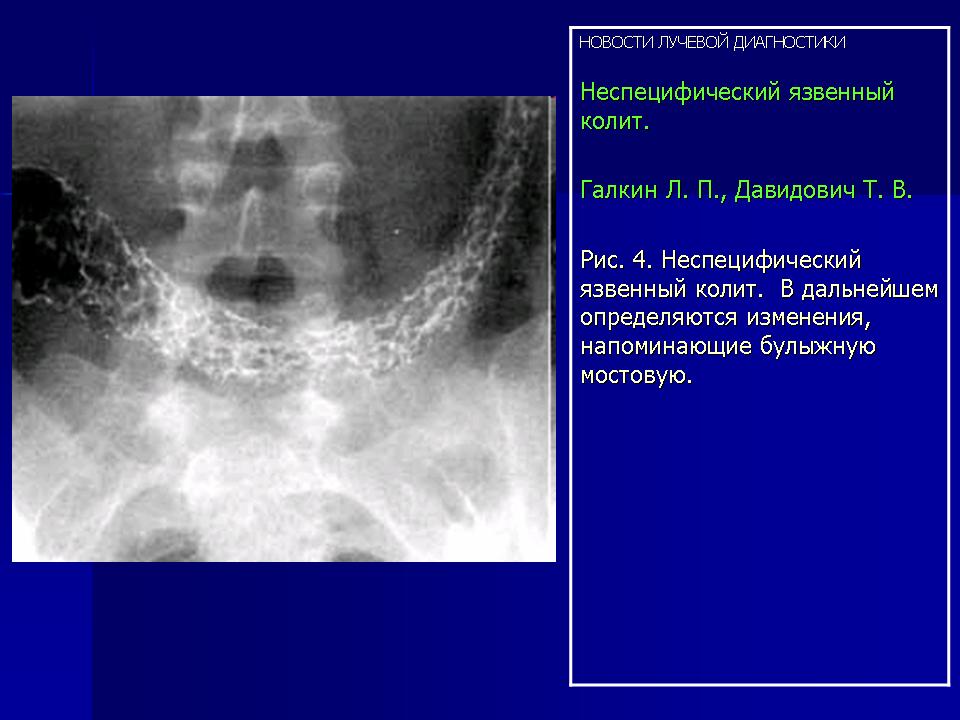

Частичное наполнение толстой кишки и двойное контрастирование обладают наибольшей информационной ценностью. На начальных стадиях колита могут обнаруживаться смазанность контура кишечной стенки, так называемый вельвето-подобный контур. Уже на этой стадии заболевания могут наблюдаться и постепенно нарастать потеря тонуса и гаустрации кишки рядом с пораженным сегментом (Рис. 2). На следующей стадии на слизистой оболочке наблюдаются мелкие пятна бария (Рис. 3) и затем изменения, напоминающие булыжную мостовую (Рис. 4). При прогрессировании заболевания, которое характеризуется распространением процесса в проксимальном направлении, могут наблюдаться не все рентгенологические находки. На кишечной стенке могут развиваться небольшие изъязвления, наполненные контрастным веществом (так называемые язвы-запонки), изолированные или на протяжении всей стенки (Рис. 5). В дальнейшем стенка кишки приобретает нарастающий мелко- или грубоволнистый контур (Рис. 6). При рецидивных обострениях отмечаются множественные, различной величины, округлые (редко — извитые) дефекты наполнения контрастного вещества. Эти изменения связаны с наличием островковых остатков слизистой оболочки, называемых псевдополипами (Рис. 7). В хронической стадии язвенного колита пораженные сегменты органа могут быть представлены как атоничные участки кишки со сморщенным просветом, без гаустрации и слизистой оболочки (Рис. 8).